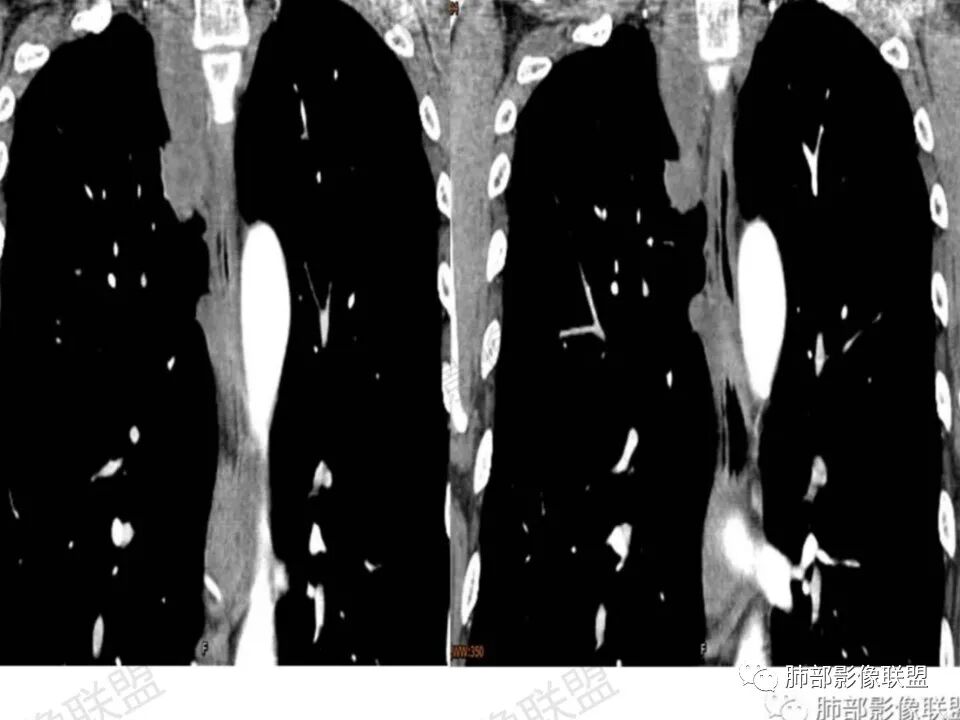

病灶内的肋间动脉穿行代表什么?

答:代表病灶内供血血管或病灶具有侵袭性将血管包绕其中。提示病灶的肺外来源属性。